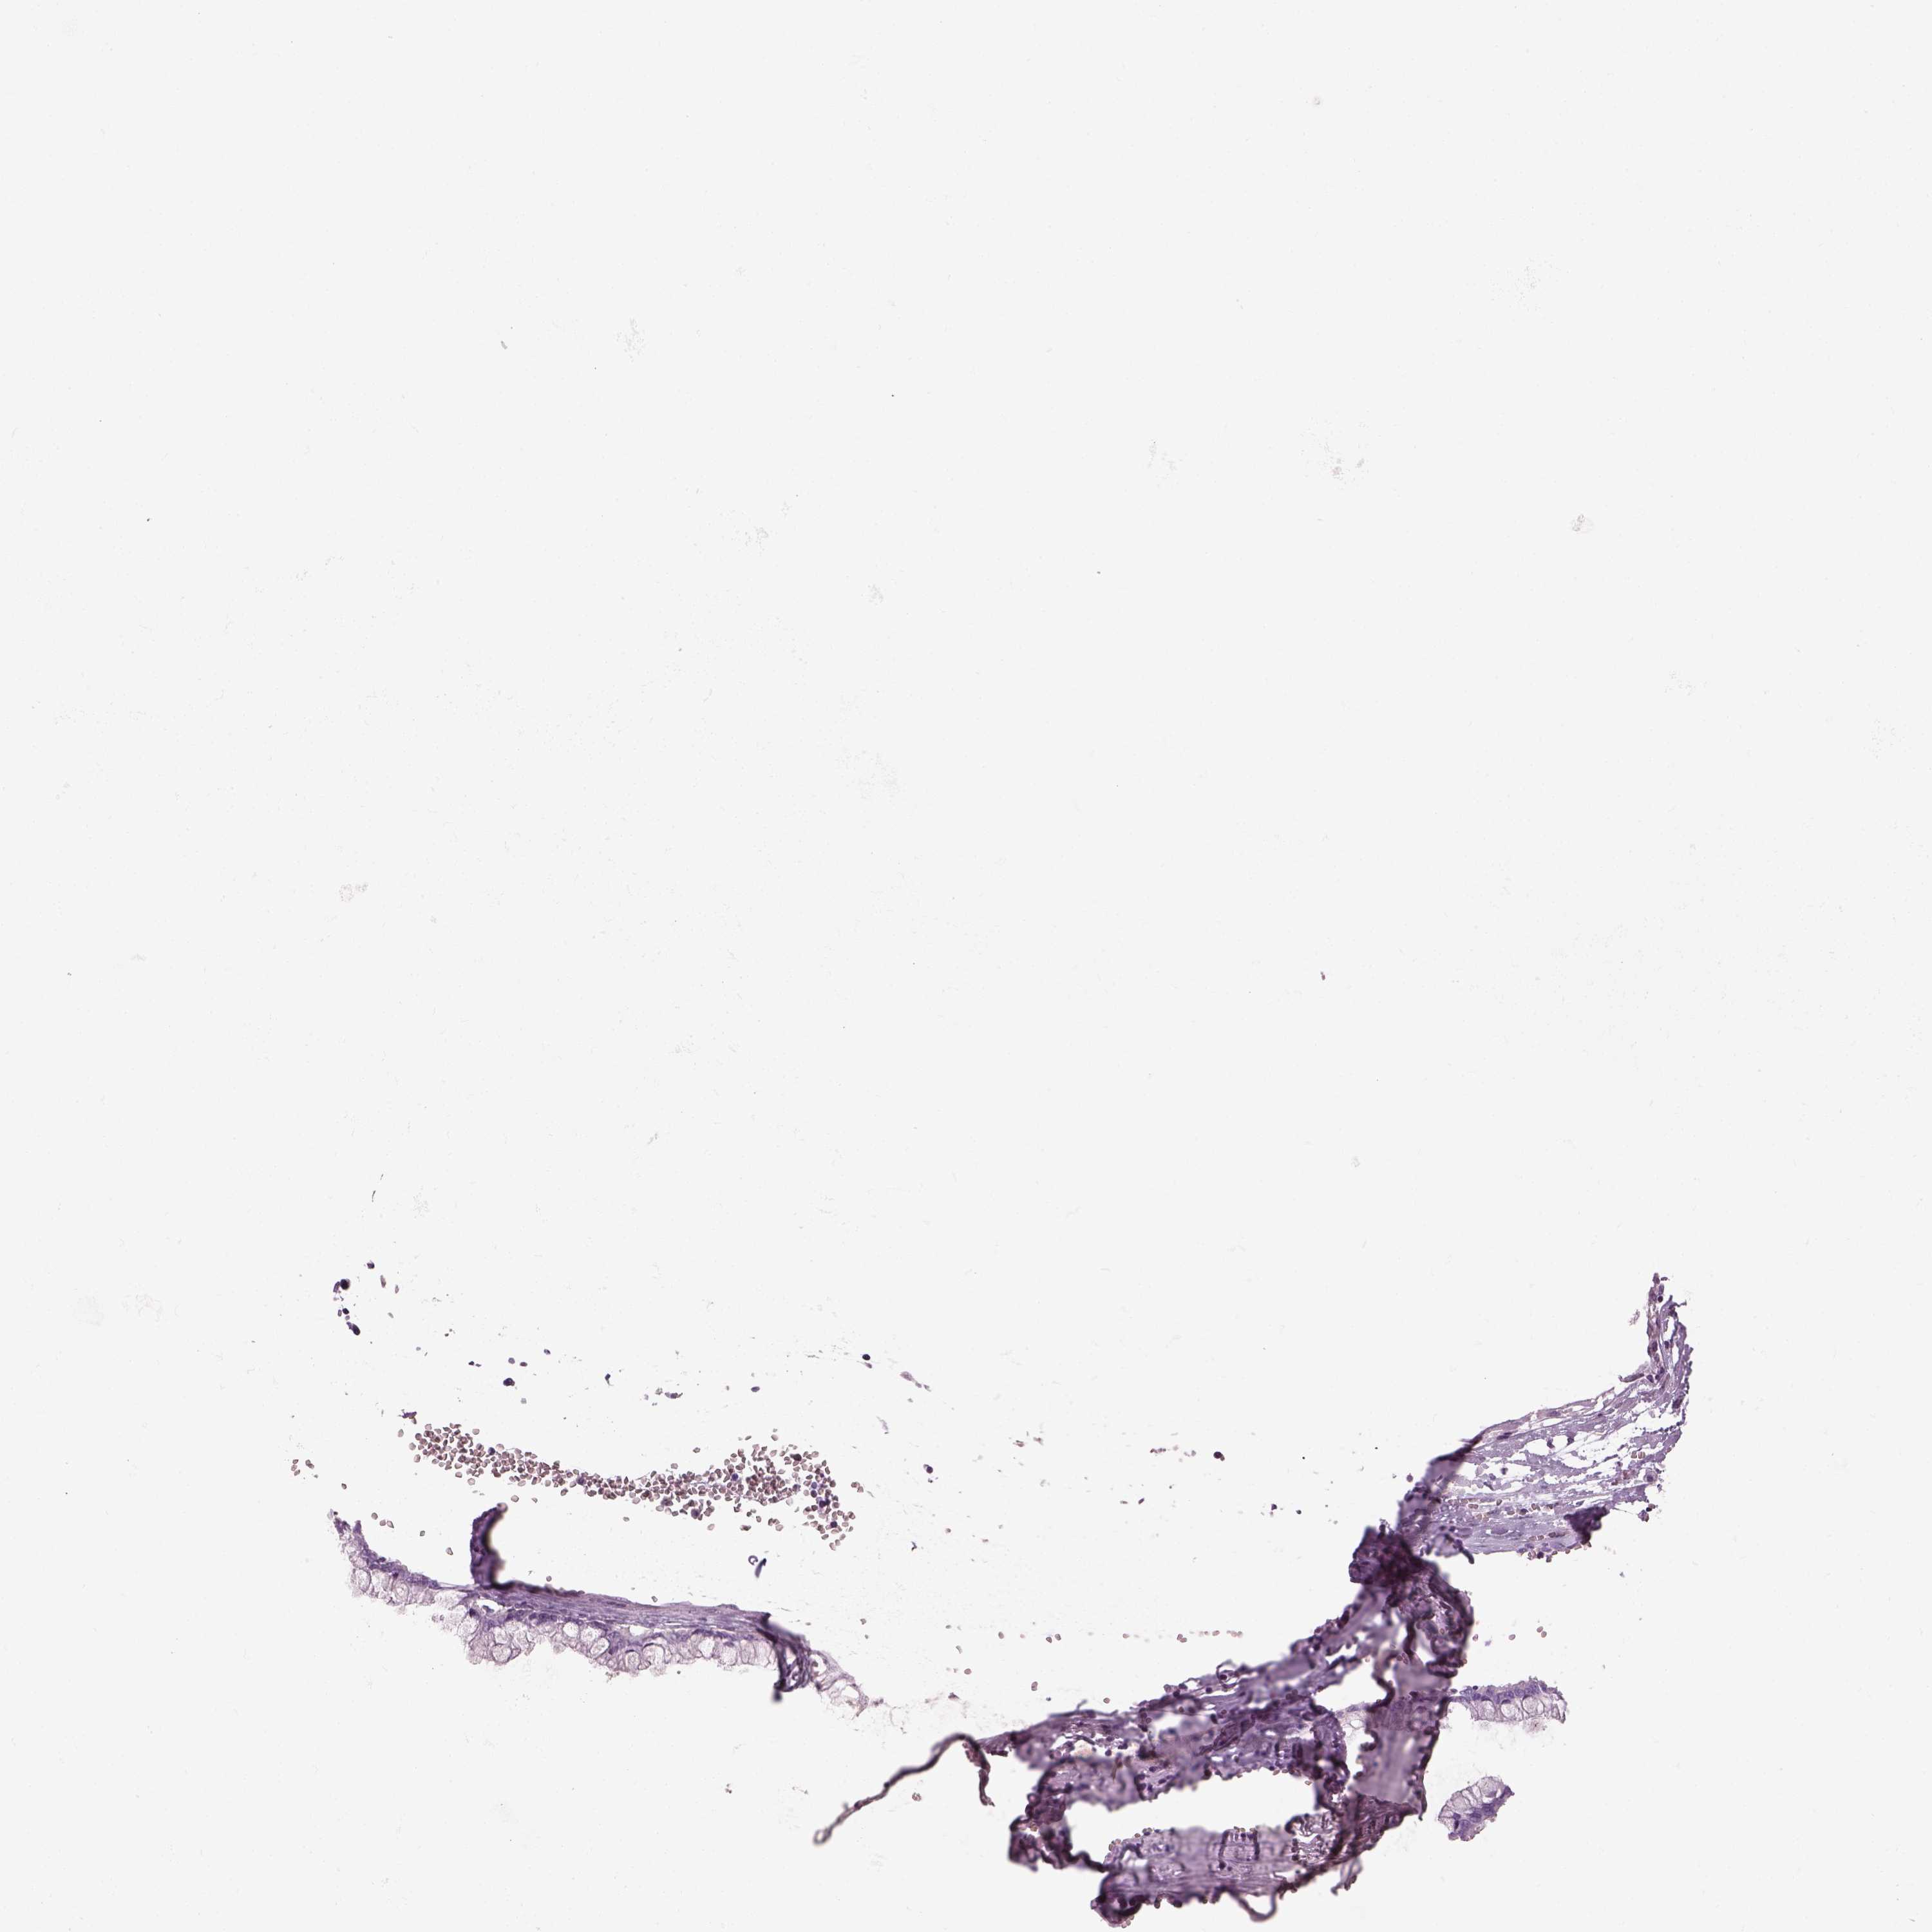

OVARIAN CANCER - Protein expressioni

A mouse-over function shows sample information and annotation data. Click on an image to view it in a full screen mode. Samples can be filtered based on level of antibody staining by selecting one or several of the following categories: high, medium, low and not detected. The assay and annotation is described here.

Note that samples used for immunohistochemistry by the Human Protein Atlas do not correspond to samples in the TCGA dataset.

Antibody stainingi

Antibody staining in the annotated cell types in the current human tissue is reported as not detected, low, medium, or high, based on conventional immunohistochemistry profiling in selected tissues. This score is based on the combination of the staining intensity and fraction of stained cells.

Each image is clickable and will lead to virtual microscopy that enables deeper exploration of all samples and also displays staining intensity scores, fraction scores and subcellular localization as well as patient and tissue information for each sample.

Antibody HPA049124

Cystadenocarcinoma, serous, NOS

Cystadenocarcinoma, mucinous, NOS

Carcinoma, endometroid